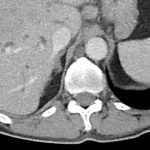

Kiefergelenksrekonstruktion

NewsZahnmedizin

Alloplastische Kiefergelenksrekonstruktion

Im vorliegenden Fallbericht einer alloplastischen Kiefergelenksrekonstruktion wird die interdisziplinäre Behandlung eines 50-jährigen komplex vorerkrankten Patienten mit beidseitiger Kiefergelenkankylose beschrieben. Durch ein abgestimmtes Therapiekonzept unter Einbezug…